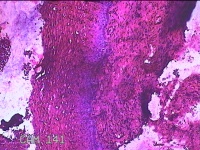

宫颈3点、6点、9点、12点组织

性别

女

年龄

38岁

临床诊断

人乳头瘤病毒感染

一般病史

发现人乳头瘤病毒感染半月。

标本名称

大体所见

1.“宫颈3点组织”:灰白暗红色组织0.8x0.7x0.2cm一块。 2.“宫颈6点组织”:灰白粉红色组织0.8x0.3x0.2cm一块。 3.“宫颈9点组织”:灰白粉红色组织0.7x0.5x0.2cm一块。 4.“宫颈12点组织”:灰白暗红色不规则碎组织1.3x1x0.3cm一堆。